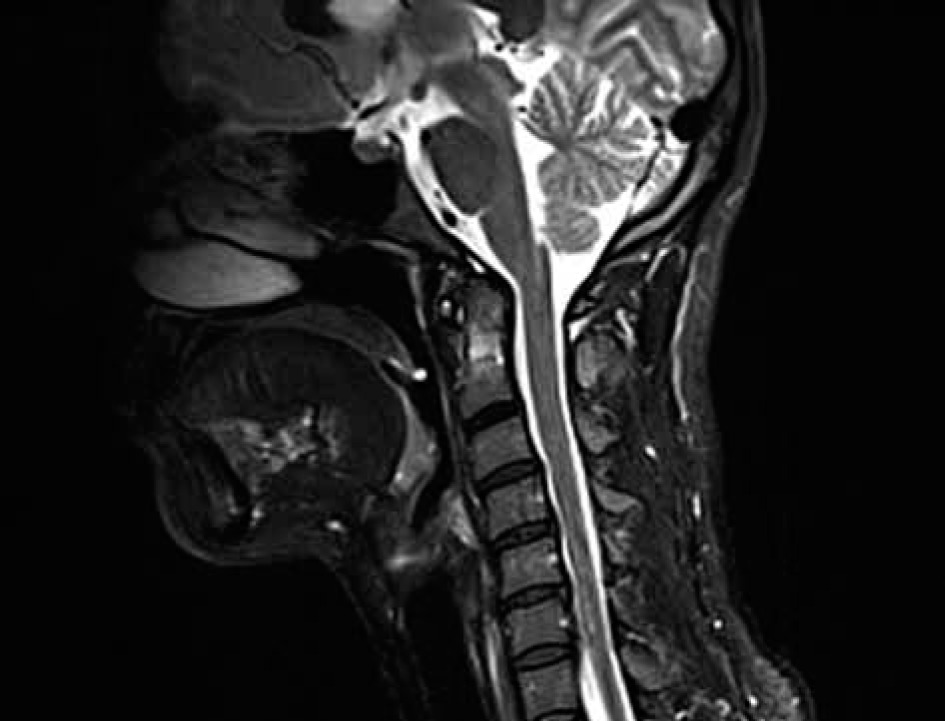

Figure 9

Sagittal MRI, T2-weighted sequence of 66 y.o. female diagnosed with RA showing multiple SAS at C3-C6 level